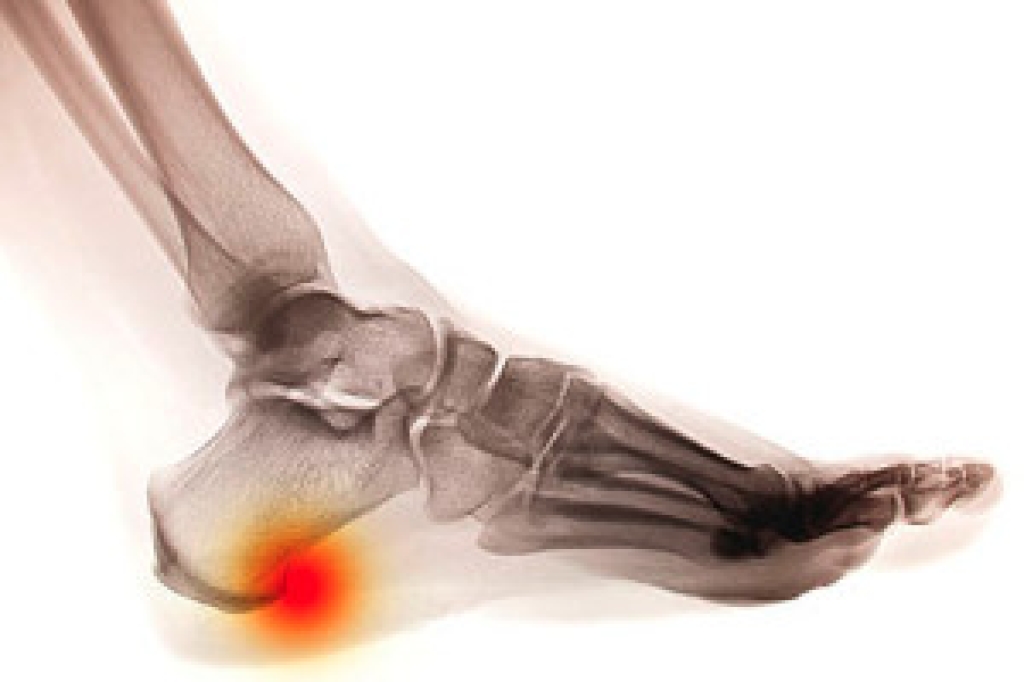

Elderly foot care issues can affect comfort, mobility, and overall quality of life. Cold feet may result from reduced circulation, changes in skin thickness, or chronic health conditions. Wounds that do not heal are another serious concern, often linked to poor blood flow, nerve changes, or pressure points that go unnoticed. These problems can increase the risk of infection and limit daily activity, if not addressed early. A podiatrist can evaluate circulation, skin health, and foot structure to identify underlying causes. Treatment may include routine foot care, wound management, pressure relief, and guidance on proper footwear. Ongoing podiatric care helps an older person maintain independence and prevents complications. If you are elderly and have any of the above symptoms, it is suggested that you schedule a visit with a podiatrist who can treat various foot and ankle conditions.

Diabetes and poor circulation can cause general loss of sensitivity over the years, turning a simple cut into a serious issue.